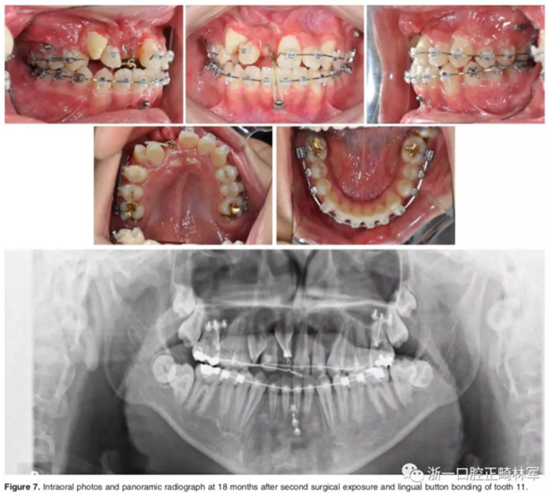

弓絲換至0.019*0.025-inch不銹鋼絲時,開始進行外科手術暴露阻生牙。由于易位情況嚴重,三維向阻擋嚴重,因此需要行兩期手術。

一期手術主要是牽引側切牙和尖牙:于上頜前牙區(qū)唇側作切口,翻全厚瓣;腭側面較??;在尖牙唇側、側切牙腭側粘扣掛結扎絲牽引,通過一輔助鈦板及樹脂等連接至弓絲上;采用閉合式導萌技術,將皮瓣復位縫合,僅結扎絲穿過粘膜;2周內(nèi)軟組織得以愈合,牽引開始。先通過正畸力,近中移動側切牙,遠中移動尖牙。10個月后,阻生牙牙冠萌出,側切牙、尖牙的易位得以矯正。

二期手術主要是牽引中切牙:于上頜前牙區(qū)腭側作切口,翻全厚瓣,在切牙唇側粘扣掛結扎絲牽引;軟組織愈合后,牽引開始。為施加合適的垂直向力,在下頜前牙區(qū)放置C型管,掛橡皮筋牽引。14個月后,切牙牙冠萌出。使用mini管代替托槽,對切牙、尖牙進行矯治;矯治過程采用輕力,0.014-in鎳鈦絲。